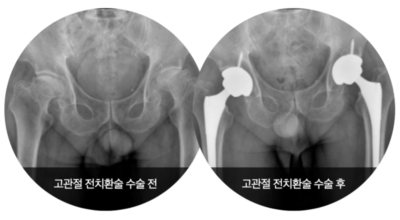

그러나 비수술 치료법으로 개선시키는 것이 어려운 경우 수술적 방법이 고려됩니다. 고관절 통증을 조기에 치료하면 약물치료 외에 물리치료로 약 50% 정도 큰 효과를 볼 수 있어요. 게다가, 보통 고관절 증상 관리에 도움되는 요가, 수영, 스트레칭은 고관절 예방과 치료에 도움 됩니다.